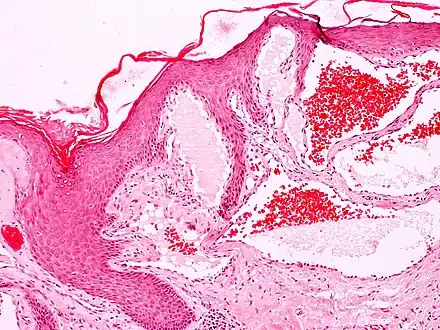

Angiokeratomas characteristically have large dilated blood vessels in the superficial dermis and hyperkeratosis (overlying the dilated vessels).

Scrotal angiokeratoma; visible large dilated blood vessels and hyperkeratosis